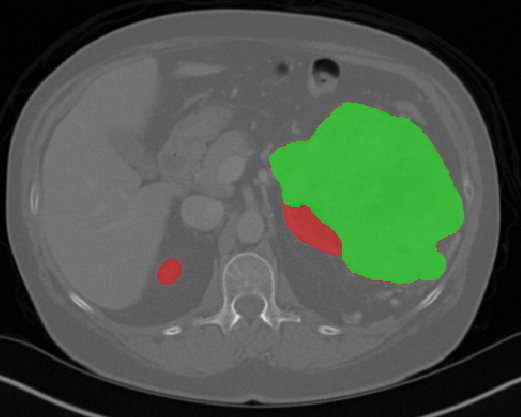

We first introduce a method for connecting the output of a CNN to an ACM, yielding a model for the precise delineation of lesions, to which we refer as Deep Active Lesion Segmentation (DALS) (Figure 4). We then go further to introduce a truly unified framework (Figure 5) that bridges the gap between ACMs and CNNs by leveraging a novel, automatically differentiable level-set ACM with trainable parameters that allows for back-propagation of gradients and can be end-to-end trained along with a backbone CNN from scratch, without any CNN pre-training. The ACM is initialized directly by the CNN and utilizes an energy functional that is locally-tunable by the backbone CNN, through 2D feature maps. Thus, our work overcomes the big hurdle of fully automating the powerful ACM approach to image segmentation. We have applied our proposed framework to the task of building segmentation in aerial images (Figure 6).

Deep Active Lesion Segmentation

[45]: Lesion segmentation is an important problem in computer-assisted diagnosis that remains challenging due to the prevalence of low contrast, irregular boundaries that are unamenable to shape priors. We introduce Deep Active Lesion Segmentation (DALS), a fully automated segmentation framework that leverages the powerful nonlinear feature extraction abilities of FCNs and the precise boundary delineation abilities of ACMs. Our DALS framework benefits from an improved level-set ACM formulation with a per-pixel-parameterized energy functional and a novel multiscale encoder-decoder CNN that learns an initialization probability map along with parameter maps for the ACM. We evaluate our lesion segmentation model on a new Multiorgan Lesion Segmentation (MLS) dataset that contains images of various organs, including brain, liver, and lung, across different imaging modalities—MR and CT. Our results demonstrate favorable performance compared to competing methods, especially for small training datasets. -